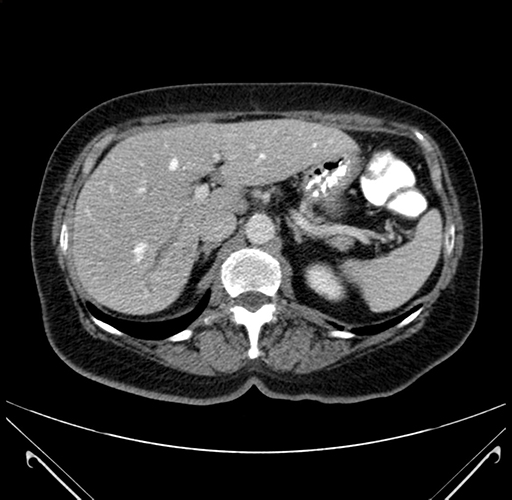

Axial Venous